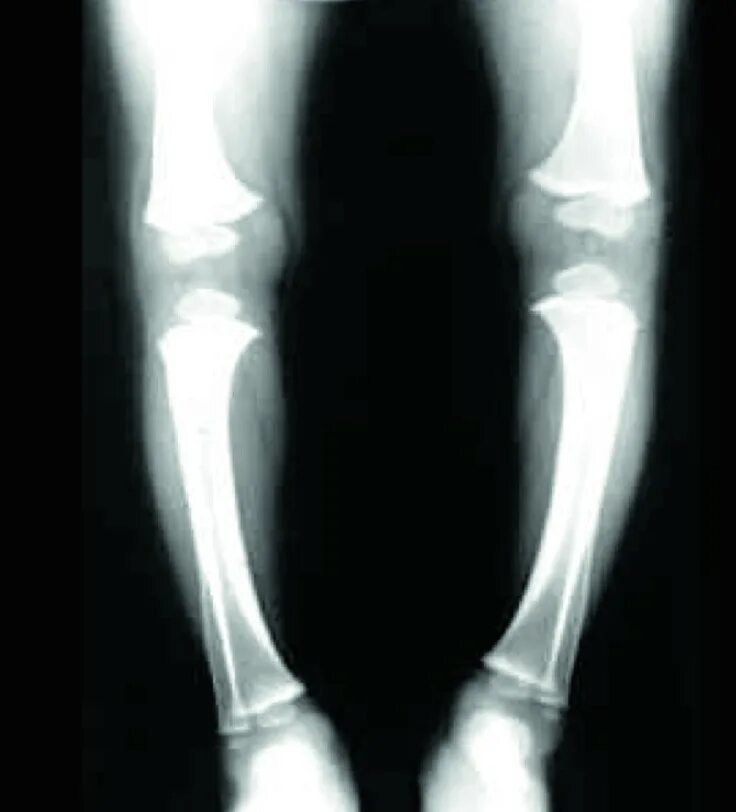

Рахит 6 лет